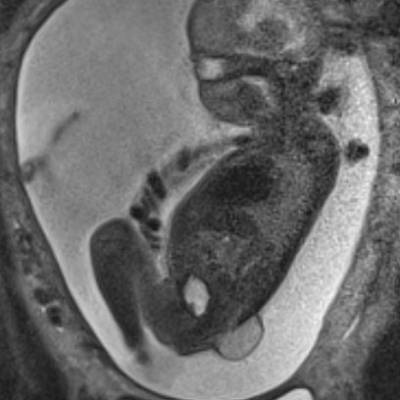

O diagnostico inicia já na consulta pre natal, não só a MMC como outras patologias são vistas e tratadas durante a gestação. Os recursos para diagnostico são a ultrassonografia morfológica, na mesma sequencia é solicitada uma ressonância magnética fetal, que é realizada com todo cuidado e é um exame inócuo para a o bebê.